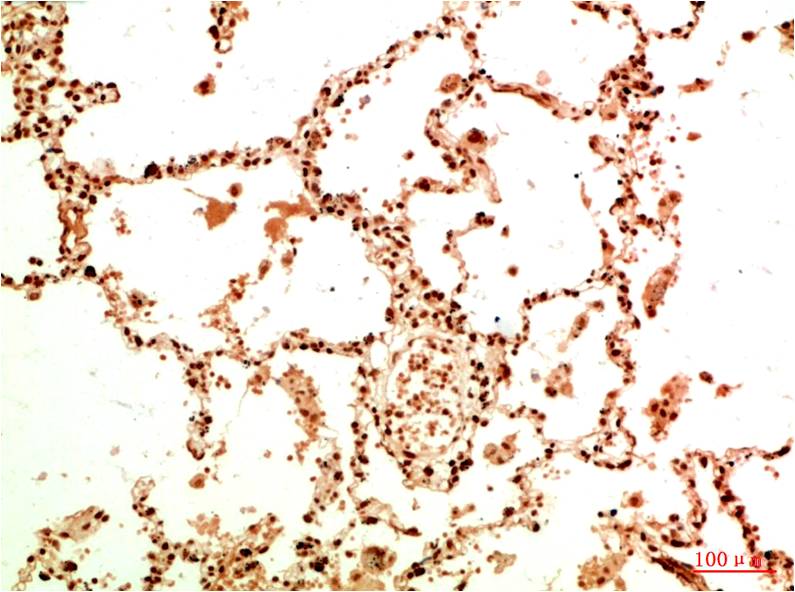

Product name: Acetyl NF kB P65(K314/K315) (5G11) Mouse mAb

Dilutions: IHC 1:100-200

Background: NFkB p65 is ubiquitinated leading to its proteosomal degradation, which is required for termination of the NFkB response. Phosphorylation of NFkB p65 on S536 stimulates acetylation of K310 by CBP, enhancing transcriptional activity. NFkB p65 is also acetylated at K122, enhancing DNA binding and impairing the interaction with NFKBIA. The protein is deacetylated by HDAC3. Invasion of a host by a pathogen is frequently associated with the activation of NF-kB, which coordinates various aspects of immune function required for resistance to infection.